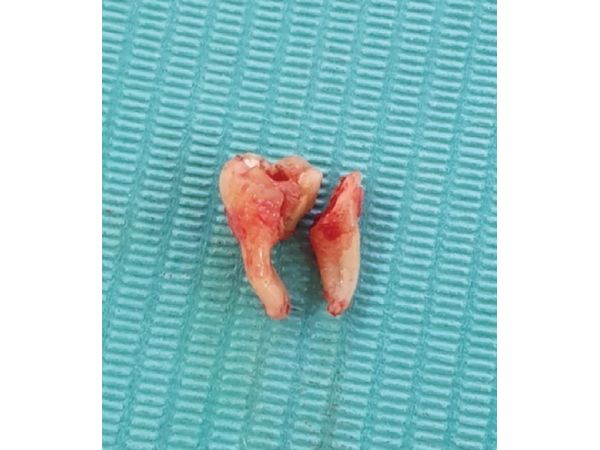

- Удалили кость над зубом, сам зуб разрезали хирургическим бором.

- С помощью прямого элеватора, который используется для вывиха и удаления корней, извлекли фрагменты зуба.